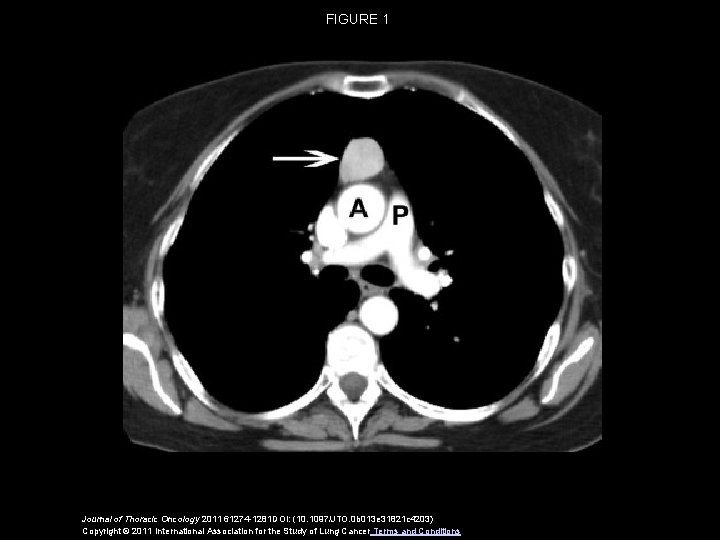

FIGURE 1 Journal of Thoracic Oncology 2011 61274 -1281 DOI: (10. 1097/JTO. 0 b 013 e 31821 c 4203) Copyright © 2011 International Association for the Study of Lung Cancer Terms and Conditions